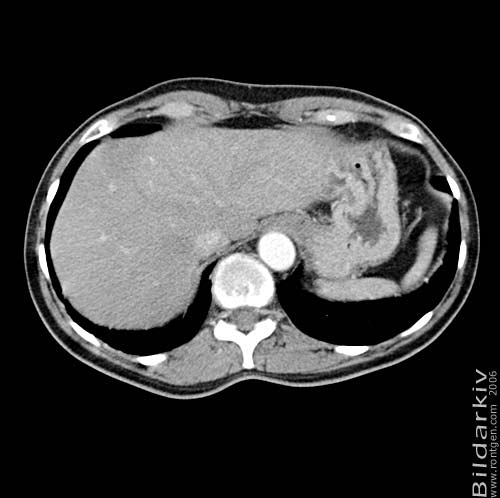

Thorax 51

Snitt över thorax med kontrast. Sk. mediastinum-fönstersättning.

CT Röntgen Helsingborgs lasarett